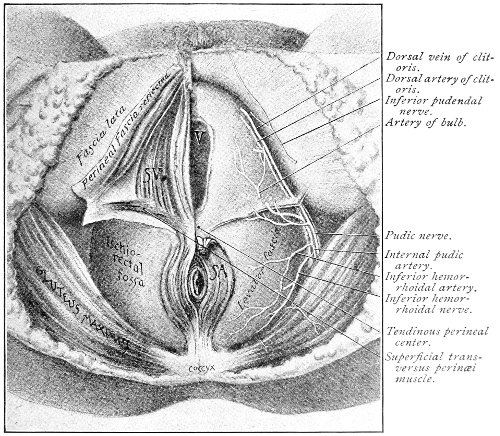

An accurate knowledge of the anatomy and mechanism of the female perineum is essential to an understanding of the nature and treatment of injuries to this structure. The anatomical structures lying between the anus behind and the symphysis pubis in front are those that most directly interest the gynecologist. Proceeding from 57 below upward, we find the following structures lying in superimposed planes: the skin, the superficial fascia, the deep layer of the superficial fascia, the transversus perinæi and the sphincter vaginæ muscles, the anterior layer of the triangular ligament, the posterior layer of the triangular ligament, the levator ani muscle (Fig. 19).

The vagina passes through these structures. They surround and support the ostium vaginæ as the fascia and muscles surround and support the opening of the rectum or the anus. The muscles and fasciæ are attached in the median line between the anus and the vagina, and therefore this part of the body, which is called the perineum, is supported or maintained in its 58 proper position by these various structures. The transversus perinæi arises from the ramus of the ischium and is inserted in the perineum. The bulbo-cavernosus, or sphincter vaginæ, arises in the perineum and is inserted in and about the clitoris. The inner fibers of the levator ani arise from the symphysis pubis and are inserted in the perineum and the lower part of the vagina (Fig. 20). When these muscles contract, their action, therefore, is to draw the perineum upward and forward. At the same time the anus is drawn upward and forward, and so also is the posterior margin of the ostium vaginæ and the lower portion of the posterior vaginal wall.

Fig. 20.—Dissection of female perineum, showing the deeper structures after removal of the levator and sphincter ani muscles.

The vagina has no circular sphincter like the anus, but 59 the vaginal month is kept closed by the action of the transversus perinæi, sphincter vaginæ, and levator ani muscles, which draw the perineum forward, and thus keep the posterior vaginal wall in apposition with the anterior wall.

Fig. 21.—Muscular floor of the pelvis seen from above.